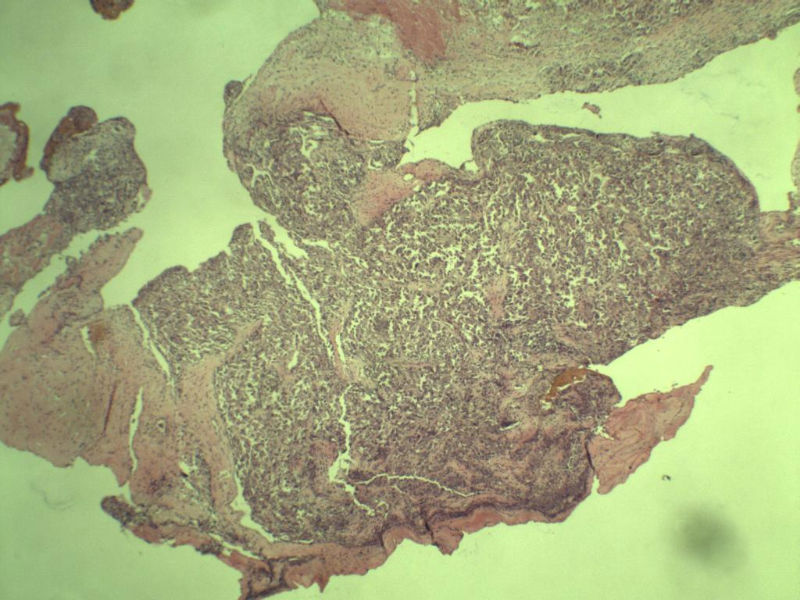

女 70岁 右颈部 头皮 多发皮下结节      取颈部部分结节送检 灰白小组织 1 块,直径 0.4 cm。 请问这个是什么?

多发皮下结节图1

melanoma

首选 恶性黑色素瘤

看不太明白,有想过恶黑,结合临床的话,那就考虑转移性的了?

肿瘤细胞大,上皮样,核空泡状,核仁明显,胞质嗜酸性或透明。

考虑:恶性黑色素瘤?

近心型上皮样肉瘤?

软组织透明细胞肉瘤?

上皮样多形性脂肪肉瘤?

等免疫组化标记!

此片染色欠佳,取材或切面也有问题,加大了诊断的难度,恶黑确实需要考虑,但其他一些转移癌也需要排除,比如肺癌之类的,还是期待免疫组化!